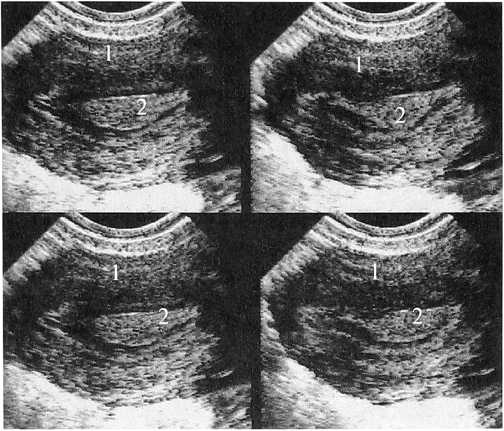

Рис. 4а. Рис. 4б.

Рис. 4а. Больная К. 35 лет. 11 день МЦ.

Два «замороженных» изображения матки до введения окситоцина. ЛУГ в эндометрии в середине полости матки. Продольное ТВ-сканирование: 1 — матка, 2 — М-эхо с ЛУГ

Рис. 46.

Два изображения матки после начала действия окситоцина. Изменение формы ЛУГ в эндометрии при сокращении стенок матки. Продольное ТВ-сканирование: 1 — матка, 2 - М-эхо с ЛУГ

При проведении ФФДП (рис. 4, 5) на фоне сокращения стенок матки отмечалось изменение формы образования из округлой — в удлиненную, с наличием заострений в месте перехода в неизмененный центральный отдел эндометрия, представляющий собой место соприкосновения передней и задней стенок полости матки (рис. 1, 2, 4, 5). У пациенток этой группы была выявлена тенденция к повышению пролактина, который на 3 день МЦ составлял от 344 до 620 мМЕ/л, ФСГ и ЛГ соответствовали верхней границе нормы, Е2 и прогестерон были не изменены. При проведении гистологического исследования эндометрия на 20—25 день МЦ были получены следующие данные: эндометрий пролиферативной или секреторной фаз с расширением просвета желез разной степени выраженности (железистая гиперплазия), в ряде случаев с наличием кистозно-расширенных желез (железисто-кистозная гиперплазия). В цитограмме аспирата диагностированы крупные пласты эндометрия пролиферативного или секреторного типа (иногда с множеством желез), без признаков атипии. При проведении ГС в полости матки определялся одиночный участок эндометрия в виде неравномерно утолщенной складки, выступа бледно-розового или красного цвета — зона локальной, очаговой функциональной гиперплазии.

Рис. 5а. Рис. 5б.

Рис. 5. Больная Т. 30 лет. 11 день МЦ.

Эндометрий соответствует пролиферативной фазе, с выраженным влиянием секреторной фазы, большой ЛУГ в середине полости матки. Продольное ТВ-сканирование: 1 — матка, 2 — М-эхо с ЛУГ; ФФДП а) — до введения окситоцина; б) — после введения окситоцина (УЗ картина напоминает одиночный крупный полип эндометрия)

Всем 120 пациенткам с ЛУГ в эндометрии (рис. 6) была назначена КГТ (бромокриптин,жанин, мерсилон, дюфастон, норколут). Через 3—6 месяцев после проведения КГТ при нормализации гормонального фона — у всех обследованных в эндометрии не определялись ЛУГ; эндометрий был однородным.

Рис. 6а. Рис. 6б.

Рис. 6. Та же больная. 11 день МЦ, через три месяца после приема КЭТ (бромокриптин).

Эндометрий соответствует пролиферативной фазе, без влияния секреторной фазы. Продольное ТВ-сканирование: 1 — матка, 2 — М-эхо без ЛУГ; а) — до введения окситоцина; б) — после введения окситоцина образования при ДН, отсутствие изменения формы и размера при ФФДП.